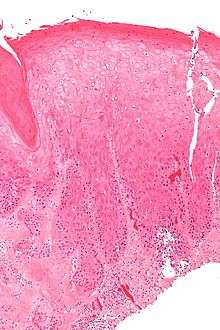

| Micrograph of (classic) vulvar intraepithelial neoplasia III. H&E stain. | |

Micrograph of vulvar intraepithelial neoplasia.